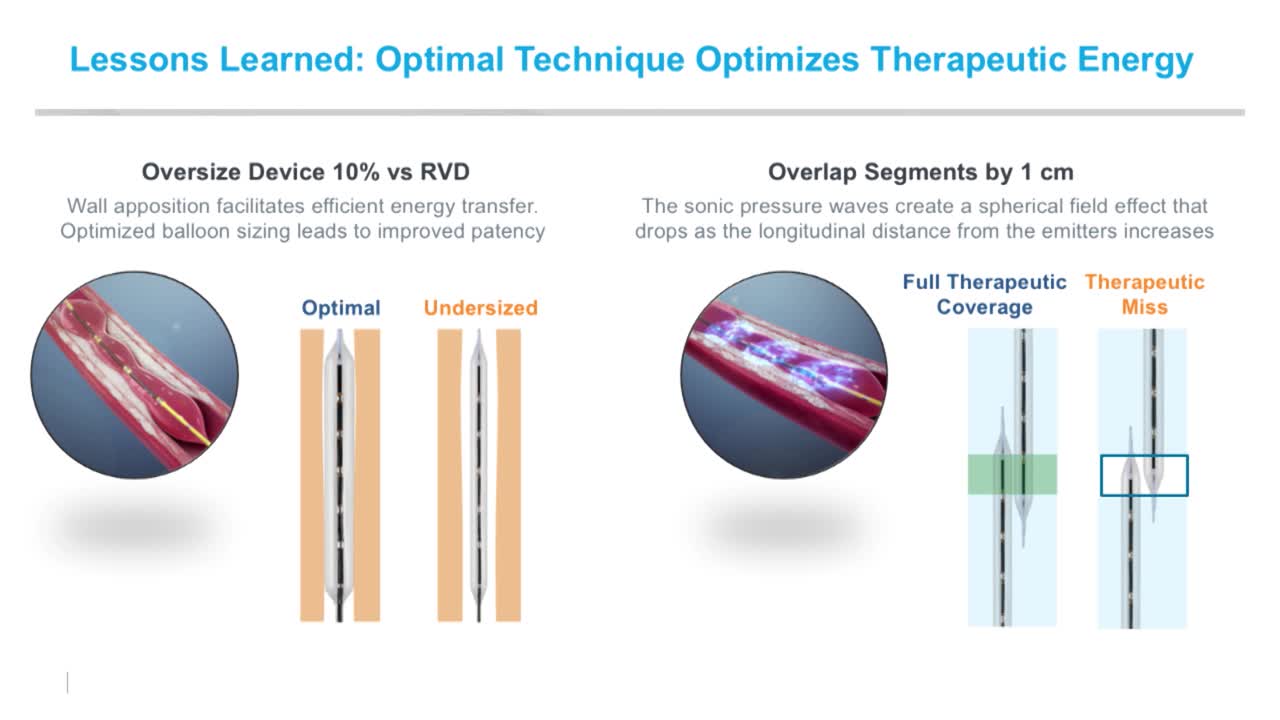

Simplify your procedures with Intravascular Lithotripsy (IVL) by safely modifying intimal and medial calcium to achieve optimal outcomes while minimising trauma, complications and costs due to its unique MOA.

Intravascular Lithotripsy for Treatment of Severely Calcified Coronary Artery Disease: The Disrupt CAD III Study

A New Wave: What’s the Future of Calcium Modification with IVL Now in the U.S.?

IVL cracking the calcium conundrum in PAD

Shockwave Experts Crack Calcium's Code